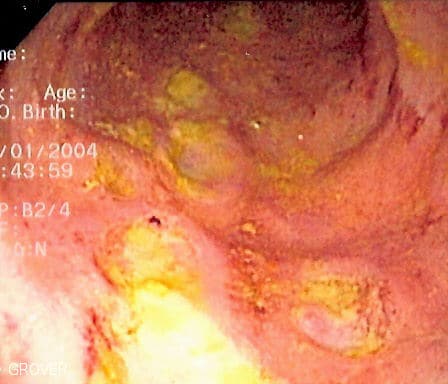

Deep Ulcerations in Crohns Disease

Colonoscopic image showing deep ulcerations and pus-like secretions found in Crohn’s Disease